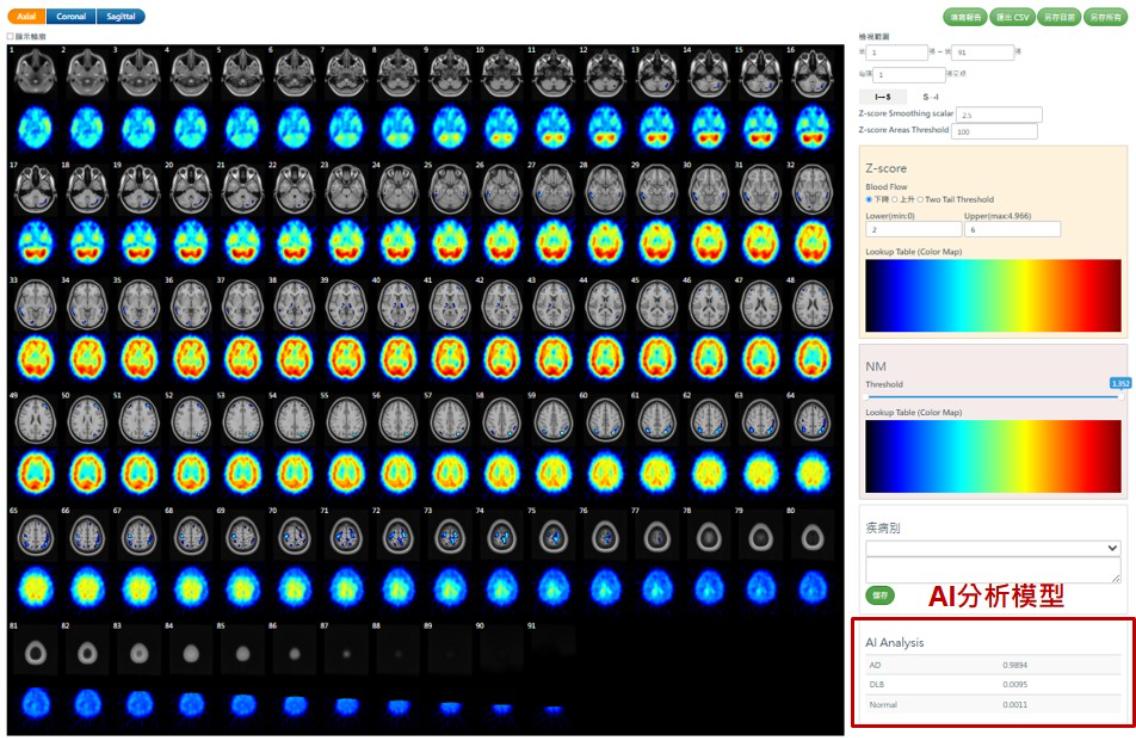

國原院近年積極投入智慧醫療研發,開發出腦血流影像異常分析軟體「ECDaim」,能自動比對腦部血流異常區域,提升影像判讀效率與準確性。研究團隊並以專利技術與機器學習演算法建立「依年齡調整的常模模板」,確保跨院影像一致性,該技術已榮獲2025年台灣創新技術博覽會資訊類鉑金獎。

亞東醫院核醫科主任汪姍瑩補充,AI系統可在資料導入後快速生成半定量Z-score分析與三維定位圖,協助醫師辨識腦區血流異常,臨床驗證顯示,AI判讀與專家結果一致性超過9成,顯示AI已成功融入診斷流程。

隨著全球阿茲海默症抗體藥物取得重大進展,早期確診的需求顯著增加,針對類澱粉蛋白沉積及神經纖維糾結的分子影像正子檢查,因而受到更大重視。汪姍瑩表示,這套AI影像分析技術能提前偵測血流異常,協助醫師「更早看見細微的變化」,提供及早確診與治療契機。